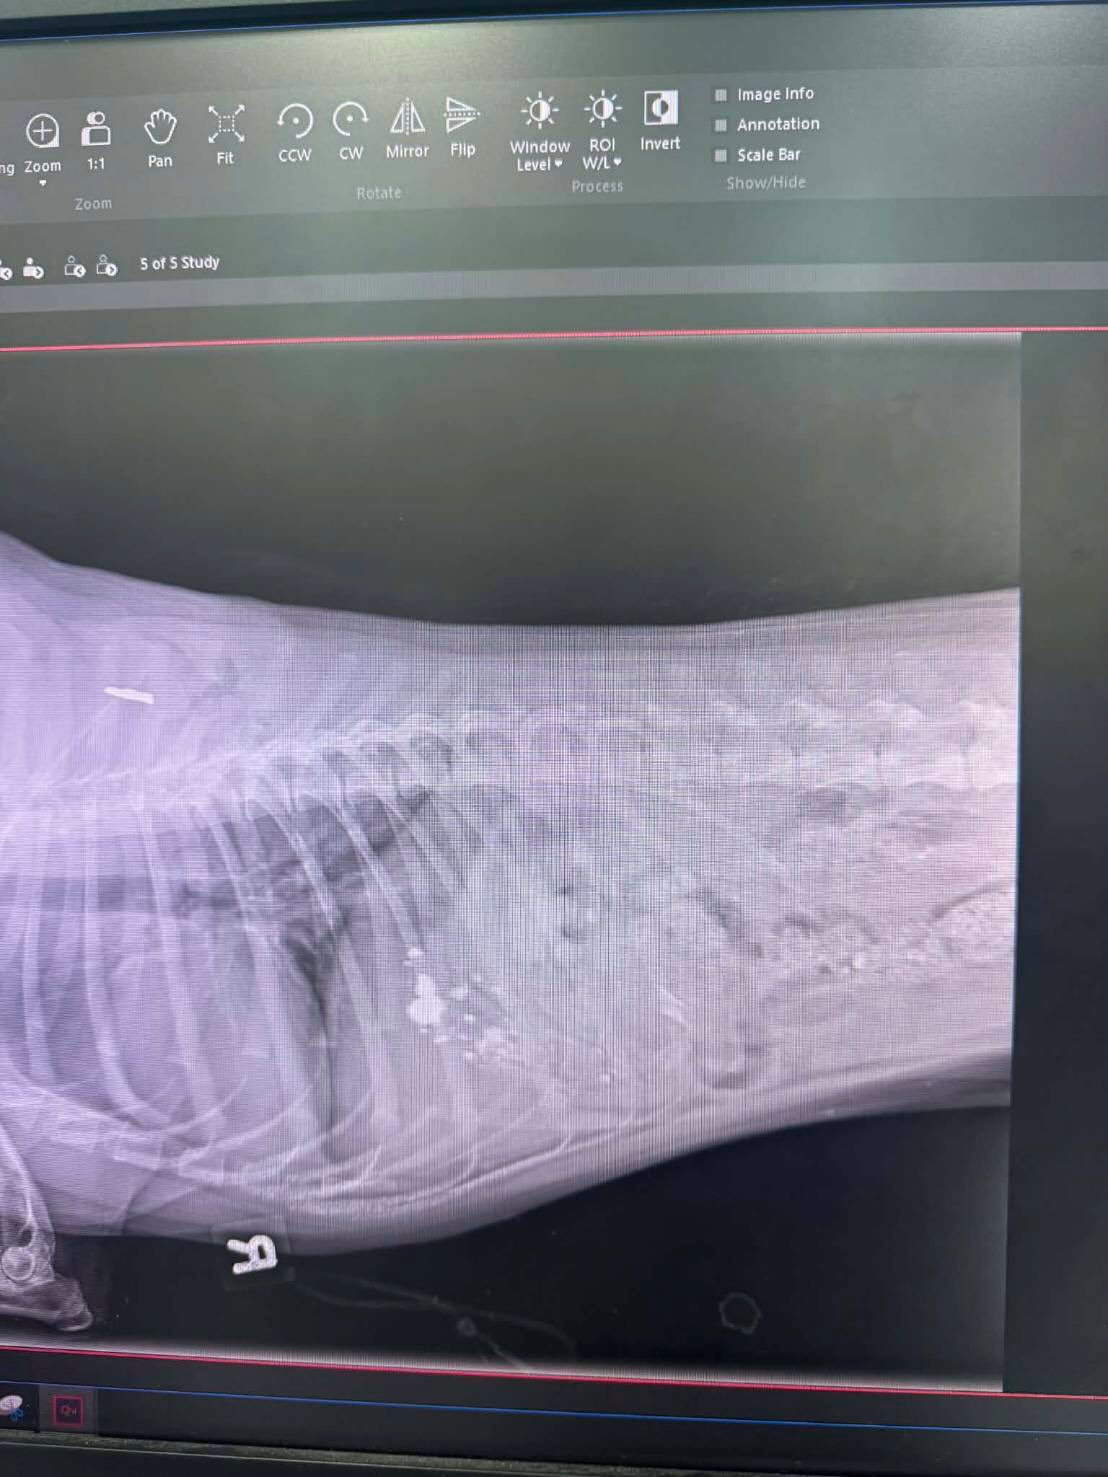

เนื่องจากมีสะเก็ดทะลุเข้าไปฝังข้างในตัวน้องบังเกอร์ บุ๋มเลยขอให้ทางทีมงานองค์กรทำดี ขับรถไปรับน้องจากโรงพยาบาลสัตว์ที่สุรินทร์ มาทำการรักษาต่อที่โรงพยาบาลสัตว์ทองหล่อในกรุงเทพฯ เพราะต้องใช้เครื่อง CT scan ตอนนี้น้องอยู่ในความดูแลของคุณหมอที่เรียบร้อยค่ะ ขอบคุณน้อง @kaechollada ที่ช่วยประสานงานให้นะคะ 🙏🏻🥰 ขอกำลังใจให้น้องบังเกอร์ด้วยครับ